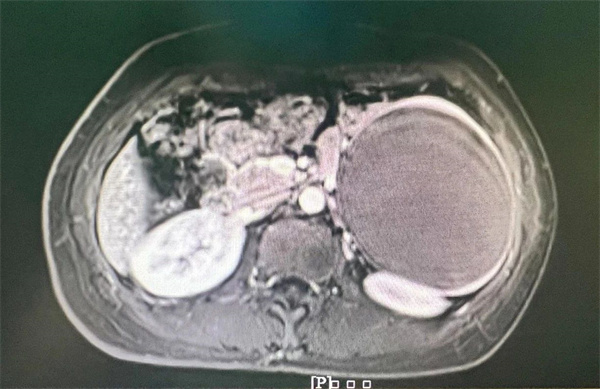

患者是一位42岁姓张的女士,过年期间进行体检时,发现脾脏一巨大肿瘤,CT提示肿瘤接近11cm,巨大的肿瘤压迫血管,需要尽快手术治疗。患者及家属辗转考虑了省外多家大型三甲医院,已经了解到做手术势在必行。

术前影像资料